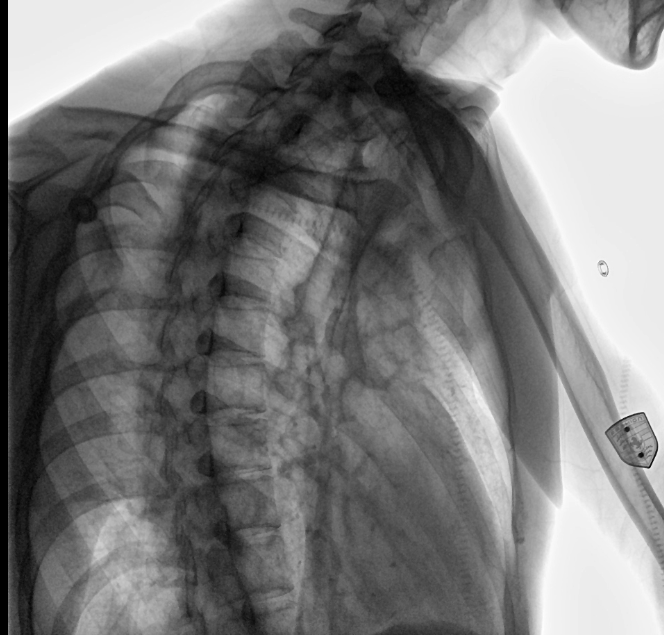

衡水市中醫(yī)醫(yī)院的放射科主任醫(yī)師于金厚主任為患者進(jìn)行檢查

設(shè)備的穩(wěn)定性,表現(xiàn)性能方面,我院現(xiàn)在這臺(tái)動(dòng)態(tài)DR,一個(gè)上午能夠接待700-800名學(xué)生進(jìn)行體檢工作,如果是使用普通設(shè)備,包含體檢人員脫衣服,擺位置,達(dá)到體檢要求在內(nèi),最快檢查速度是2-3分鐘,但沒有透視功能,無法承載這么多的量,而且需要2位醫(yī)師輪換操作。

衡水市中醫(yī)醫(yī)院的放射科主任醫(yī)師于金厚主任操作國(guó)產(chǎn)DR設(shè)備